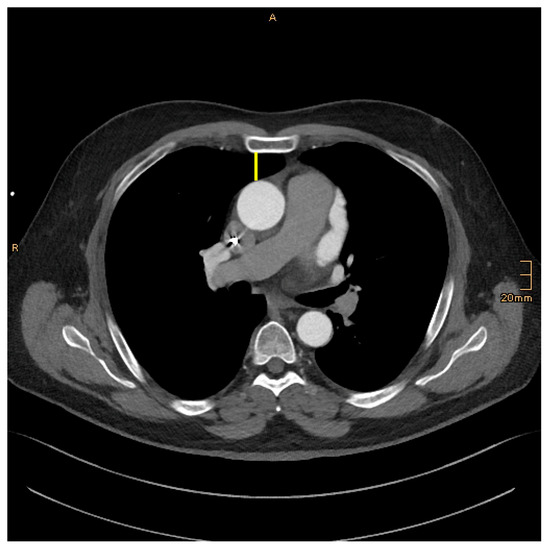

DSA–Distance between the sternum and aorta: On an axial image, just above the right atrial appendage.

Figure 2. DSA–Distance between the sternum and aorta: yellow.